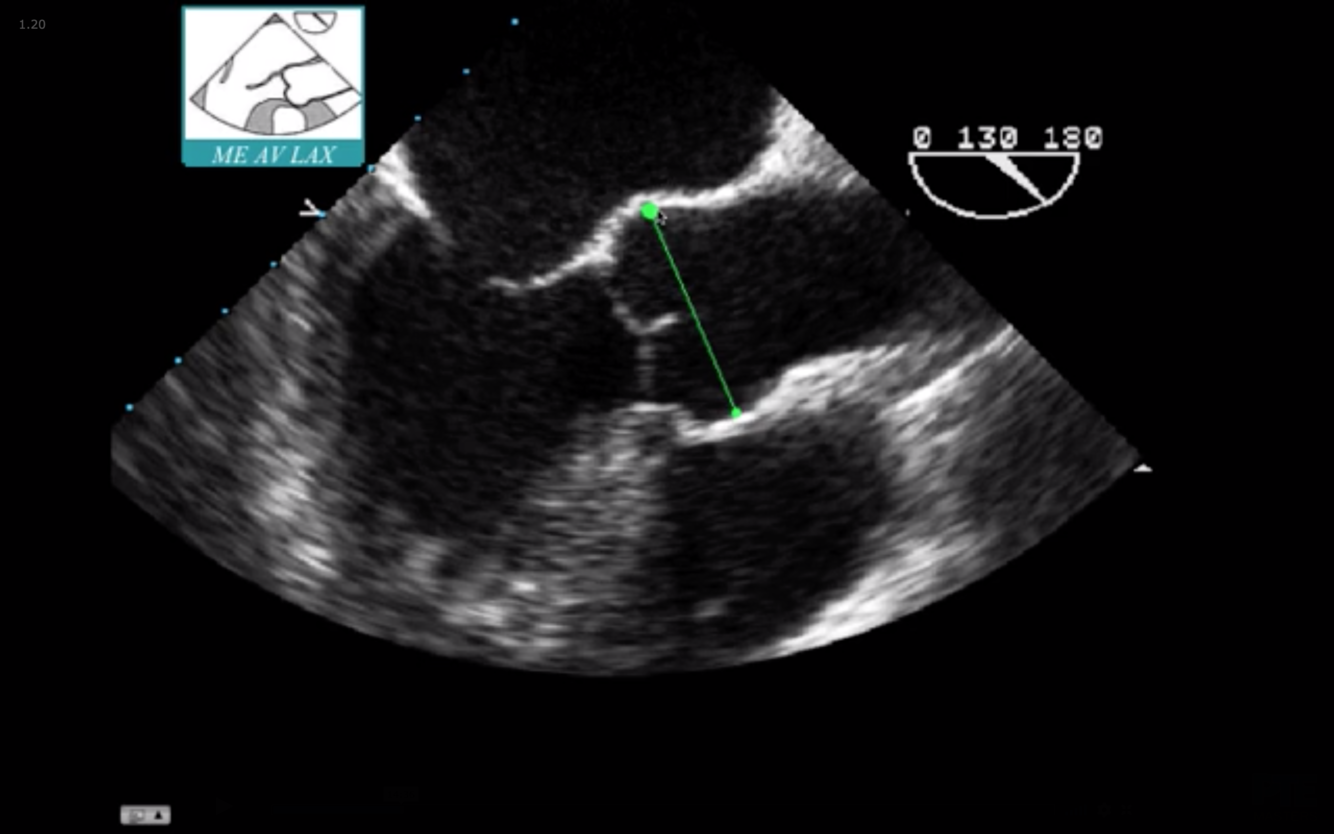

What is the measurement seen here?

Sinus of Valsalva

What is seen in red?

Aortic Annulus